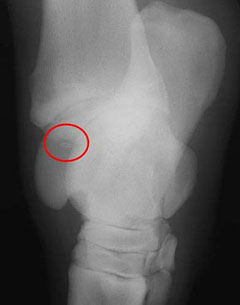

This is an example of how an OCD fragment typically looks on a radiograph. The OCD fragment seems to “float” within a defect in the main bone